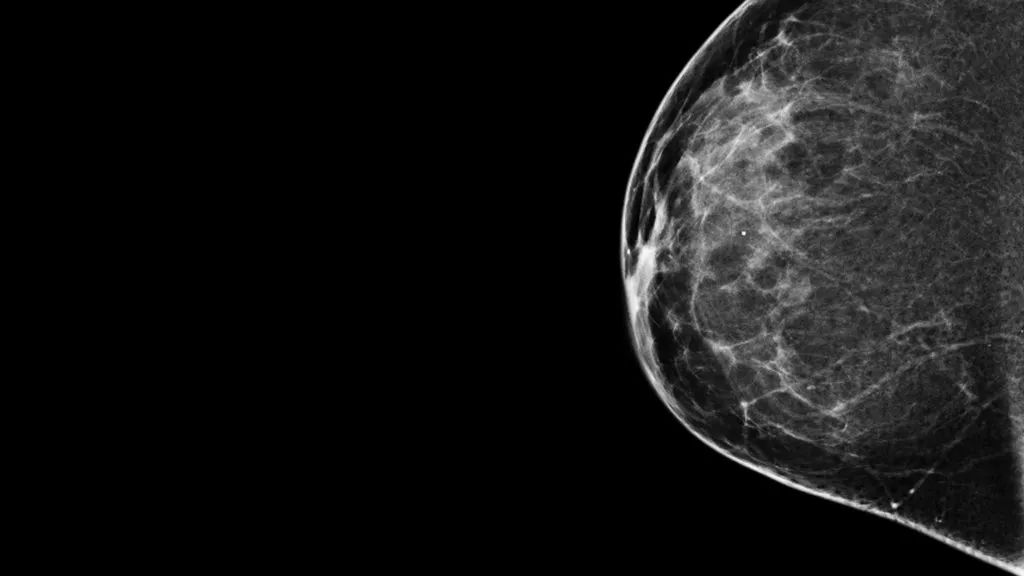

乳腺篩查是女性體檢時的常規(guī)項目,對發(fā)現早期癌變,提高乳腺癌患者的生存率有重要意義[4]。微小鈣化是乳腺篩查時常見的現象,在乳腺成像中,微小鈣化一般表現為直徑小于1mm的小亮點。目前已有多篇報道指出,微小鈣化與多種心臟代謝疾病相關聯(lián)[5],且乳腺密度也與吸煙及BMI等心臟代謝疾病的主要危險因素相關。

乳腺圖像特征與多種心臟代謝疾病的關聯(lián)性分析結果